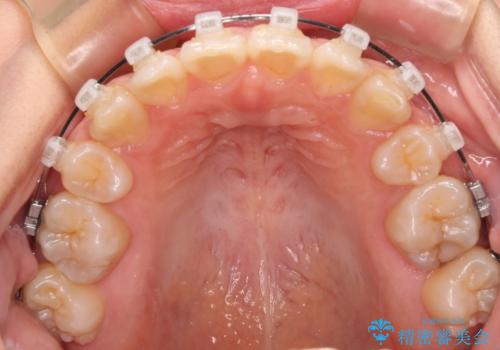

- クリアブラケット

- 2年6ヶ月

- 10-30回

また、開咬を改善するため臼歯部にアンカースクリューを用いて圧下する力をかけていきました。

舌のトレーニングは継続して行ってもらっているため、開咬や抜歯したスペースの後戻りはなく、経過は良好です。